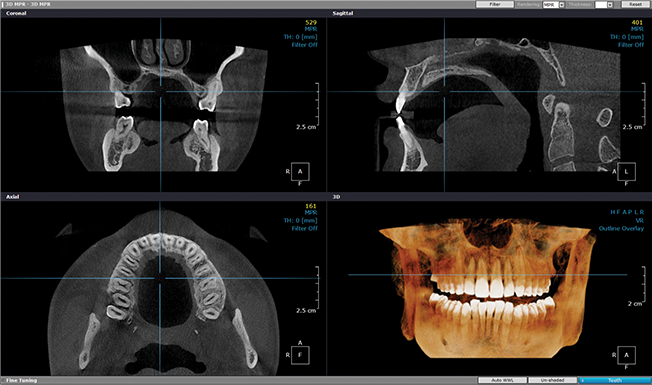

임플란트 치료과정

진단 및 치료 계획

방사선, 혈액검사, 초음파를 통해 치료계획 수립 후 상담을 통해 치료 방법을 결정합니다.